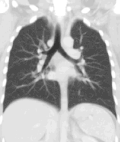

A CT scan can be used for detecting both acute and chronic changes in the lung parenchyma, the tissue of the lungs.[66] It is particularly relevant here because normal two-dimensional X-rays do not show such defects. A variety of techniques are used, depending on the suspected abnormality. For evaluation of chronic interstitial processes such as emphysema, and fibrosis,[67] thin sections with high spatial frequency reconstructions are used; often scans are performed both on inspiration and expiration. This special technique is called high resolution CT that produces a sampling of the lung, and not continuous images.[68]